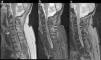

At 2 days after the trauma, magnetic resonance imaging of the cervical region was carried out, where cervical canal stenosis was observed. Fusion of C4–C5 vertebrae. Signs of spinal cord contusion from C3 to fused vertebrae (C4–C5). No evidence of intracanalicular bleeding or other processes that compromise space. Oedema in posterior interspinous ligament (Fig. 2).

Cervical MRI study on sagittal planes, sequences FSE T2 (a), STIR (b) and GRE T2* (c). In the FSE T2 and STIR sequences, significant canal stenosis in C3–C4 is shown, with hyperintense spinal cord signal (thin arrows), in relation to oedema secondary to spinal cord compression. Congenital vertebral fusion of C5–C6 is also identified, with a very rudimentary disc (thick arrow in “a”). In the STIR sequence, oedema between the spinous processes C4–C7 and adjacent paraspinal muscles is identified, in relation to partial injury to the interspinous ligaments (thick arrows in “b”). The gradient echo sequence T2* shows an intramedullary hypointense linear image at C3 and another punctiform at C5 in relation to haemorrhagic content (arrows in “c”) a finding for a poor prognosis.